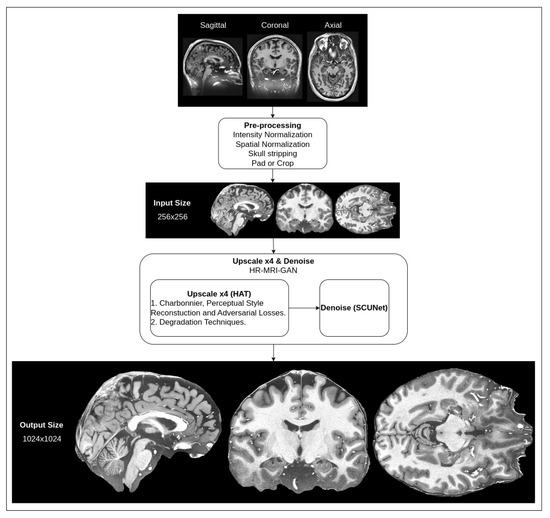

3. Materials and Methods

3.1. Upscale Network

3.2. Denoise Network

4.1. Experimentation Data

4.2. Implementation Details